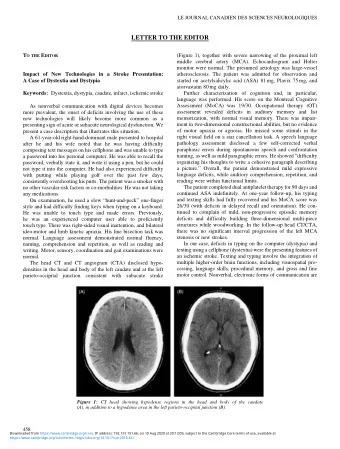

Thrombolysed patients 2 4 6 8 10 12 14 16 18 20 Jan- 11 Feb- 11 Mar- 11 Apr- 11 May- 11 Jun- 11 Jul- 11 Aug- 11 Sep- 11 Oct- 11 Nov- 11 Dec- 11 Jan- 12 Feb- 12 Mar- 12 Apr- 12 May- 12 Jun- 12 Jul- 12 Aug- 12 Sep- 12 Oct- 12 Nov- 12 Dec- 12 Jan- 13 Feb- 13 Date Patients

slide-10

Increase in Thrombolysis

20 40 60 80 100 120 140 year 2009 year 2010 year 2011 year 2012

Thrombolysed patients by year

Thrombolysed patients

slide-11